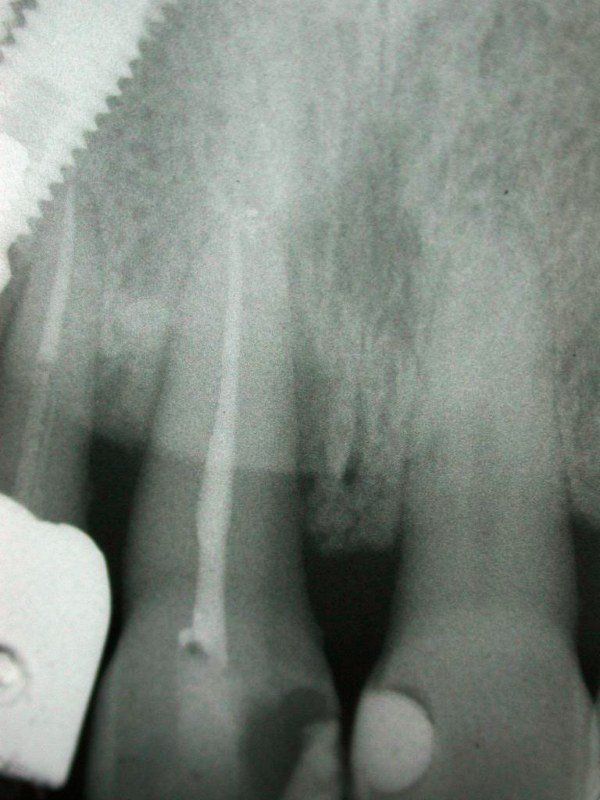

1° Caso: retrazioni gengivali